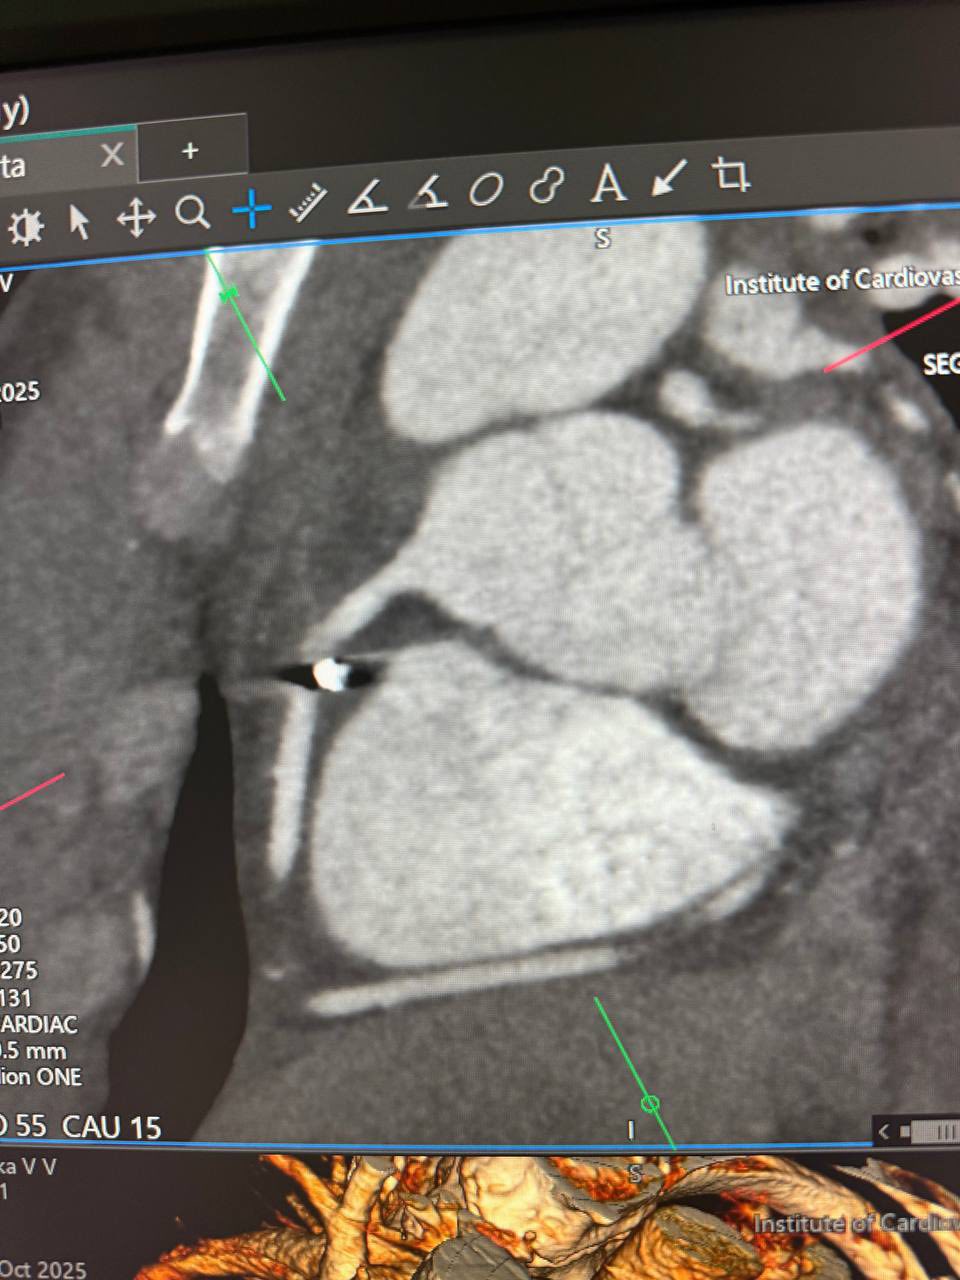

Металевий фрагмент застряг у правій атріовентрикулярній борозні, поруч із правою коронарною артерією — надзвичайно небезпечною ділянкою, де будь-який рух може коштувати життя. Операцію провів директор Інституту, академік Василь Лазоришинець, разом із командою фахівців.